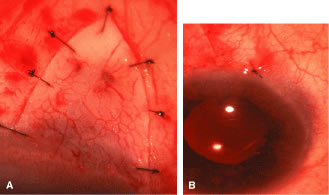

the 10 and 2 o'clock positions of the eye, assumes great significance.  Fig. 9. Indentation gonioscopy. A. The angle appears closed. However, the observer cannot determine whether

this appearance is due to mere contacts between the iris and cornea

or to actual adhesion. B. The goniolens has been pressed against the central cornea, displacing

aqueous into the periphery and showing that the angle is open. C. Indentation gonioscopy displaces the iris posteriorly, showing peripheral

anterior synechiae. (Schwartz LW. Diagnostic evaluation of the patient. In Spaeth GL (ed). Early

Primary Open-Angle Glaucoma: Diagnosis and Management. Boston: Little, Brown & Co, 1979.) Fig. 9. Indentation gonioscopy. A. The angle appears closed. However, the observer cannot determine whether

this appearance is due to mere contacts between the iris and cornea

or to actual adhesion. B. The goniolens has been pressed against the central cornea, displacing

aqueous into the periphery and showing that the angle is open. C. Indentation gonioscopy displaces the iris posteriorly, showing peripheral

anterior synechiae. (Schwartz LW. Diagnostic evaluation of the patient. In Spaeth GL (ed). Early

Primary Open-Angle Glaucoma: Diagnosis and Management. Boston: Little, Brown & Co, 1979.)